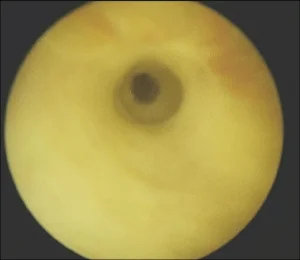

Patient is asked to drink water and inform us when he wants to pass urine. He is then requested to urinate in a special toilet which is connected to a computer. Normal urine flow is smooth and bell-shaped curved. Speed to urine is about 15-20 ml/sec. In stricture this flow decreases